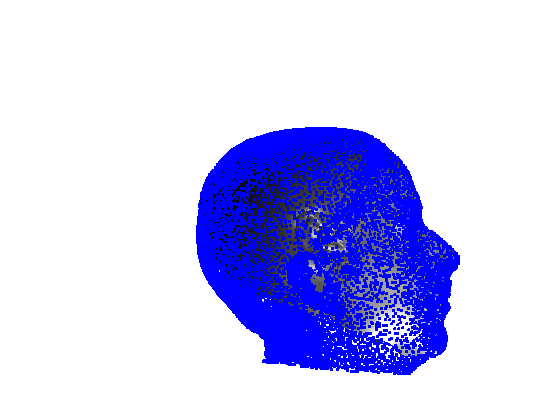

Toolsets to define normal appearance and therefore both assist with planning of surgery and define optimal outcomes from a range of surgical interventions are currently either crude or lacking. Therefore, the unit collected a large, high quality 3D image dataset of 1523 human heads. An example is given in Fig. 1 showing the 3D channel only on the left, and the 3D data with texture pasted on on the right. The data was collected over well-conserved demographics, and an age range of 1 to 89 years, see Fig. 2. The dataset was collected with the aim of developing a normal equivalent of the human cranium and face in order develop the tools to enhance patient experience following surgery. We plan to make the dataset publicly available in the near future.

Our system can accept 3D images in arbitrary pose and employs an automatic landmarking scheme to normalise the pose of the 3D head before any further processing. Two examples of typically varying initial pose taken from the headspace datset are shown in Fig. 4.

Fig. 9 shows examples of the fitted model (trained on FRGC data) on the first four subjects in our Headspace training set. Note that the mean of the landmarks in the sparse model is centred on the orgin, and so the scan data is moved towards that and becomes frontal in pose. We note that other researchers [28] have used 3D landmark localisation to find the head, but often this only includes landmarks that are relatively easy to localise, namely inner eye corners and nose. Localising more landmarks over a wider facial area has a number of advantage in terms of cropping, pose normalisation and global 3D template warping, all of which are described later.

7 Extension to 3D full head modelling

Pose is normalised using the ECN method, and relies on the symmetry plane, ellipse centre and nasion position, as shown in Fig. 25. We then find a set of pseudo-landmarks on the cranial surface by 3D ray projection over a predefined set of angles, as shown in Fig. 26. The same processes are applied to a template mesh of the human head, so that it has the same set of both face and cranium landmarks.